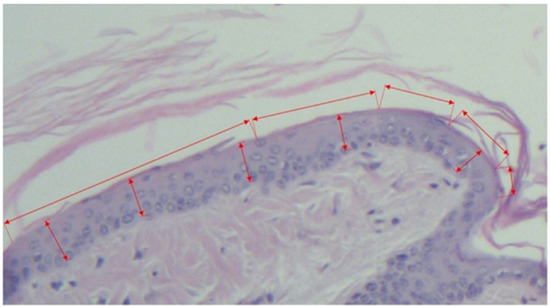

- Horizontal length of the scale, measured as the distance between two follicles including the sebaceous gland (see Figure 1 and Figure 3).From the values obtained at A-B the secondary parameters were obtained [4]:

- Mean epidermal thickness of the individual scale (between two pilous follicles). For mean epidermal thickness, 5 measurements were made in each of the 10 scales, resulting in 300 measurements per group. The dimensions were calculated in micrometers.